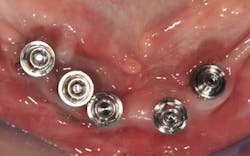

Mandibular arch: the lower jaw is fully edentulous. Initially, according to the patient, an implant-supported five-unit bridge (23 to 27) was made on four implants (Alphabio®) placed in 2007. Tooth 22 was present at the time and a removable partial denture replaced the bilateral posterior missing teeth.

Then, in January 2012, tooth 22 was extracted and a second implant specialist placed a new implant (Zimmer Dental®) to replace it. The GP decided to use a Locator® attachment system on this new implant and have the existing denture stabilized over it, without paying any attention to the collapsing situation of the upper right.Fig. 3: CT scan shows the existing implants positions and the bone volume available

Fig. 7b: The positioning of the transfer copings already shows inadequate implant positions

Fig. 7c: Transfer coping placement on site 26 is impossible: this implant will have to be removed or submerged